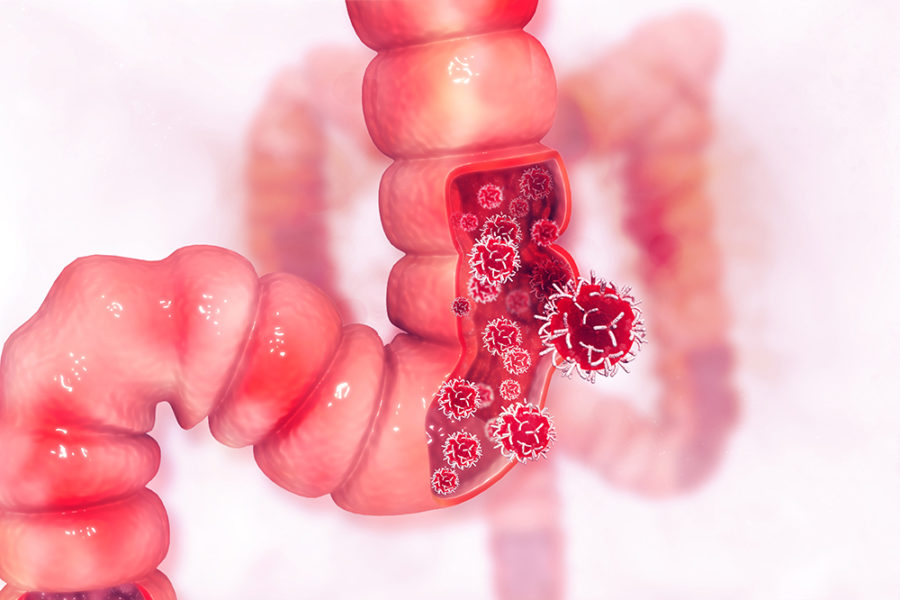

Der Darmkrebs (Karzinom) ist eine der häufigsten Tumorerkrankungen. Dabei wird zwischen Dickdarmkrebs (Kolonkarzinom) und Mastdarmkrebs (Rektumkarzinom) unterschieden.